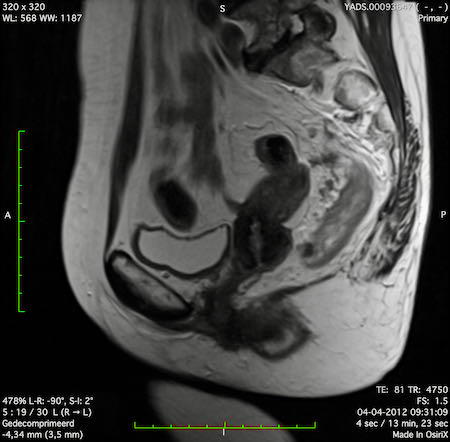

Hình ảnh

Các hình ảnh được cung cấp cho thấy ung thư biểu mô tế bào nhẫn với tình trạng dày lan tỏa thành trực tràng, hình ảnh bia bắn điển hình, và sự xâm lấn mỡ mạc treo trực tràng.